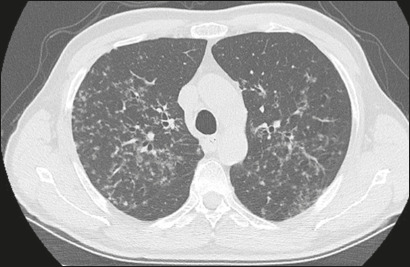

Results: Forty-nine patients (30 males; mean age, 61 years) were included. We identified Gram-negative bacteria in 45 patients, Gram-positive bacteria in 13, and fungi in three. Pulmonary abnormalities were bilateral in 73% of the patients in the sample, and there was no difference in prevalence between the upper and lower lung fields in 53%. Common alterations were consolidation, in 73% of the patients, bronchial wall thickening, in 71%, bronchiectasis, in 55%, and nodules, in 53%; extrapulmonary findings were less common, being identified in ≤ 27%. Pulmonary findings were typically bilateral and without a predominance between the upper and lower lung fields (p < 0.05). Common associations were between consolidation and bronchiectasis, between nodules and bronchial wall thickening, and between bronchiectasis and bronchial wall thickening (p < 0.05 for all).

Conclusion: The CT manifestations of pneumonia in patients with hematologic diseases not responding to empirical therapy can resemble those of lobular pneumonia with airway inflammation. For that reason, as well as because multiple pathogens can be present in the same patient, examination of bronchoalveolar lavage fluid can be necessary.